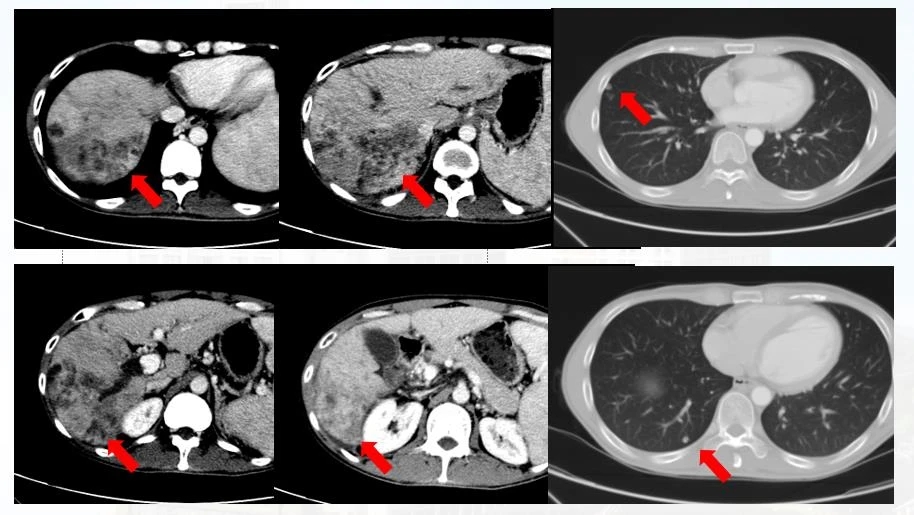

第四个疗程后复查CT( 2020-08-4,见上图 ),肝内肿物较前明显缩小、减少,门脉癌栓范围较前缩小,肺内病灶较前进一步缩小。

患者入院时胆红素为81.3umol/L,治疗一次后尽管升至99.7umol/L,但继续动脉灌注化疗后持续下降,最近复查降至25.6umol/L,患者的症状较前明显好转。